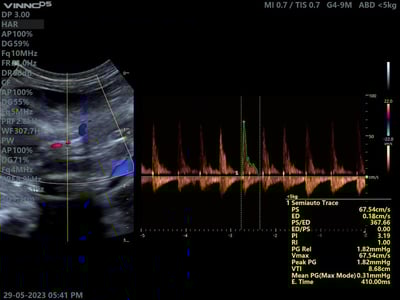

Estudio con Ultrasonido VINNO 5 con transductor micro convexo G4-9M usando Doppler pulsado con mediciones automáticas y Doppler color para visualizar vena cava, aorta y porta.